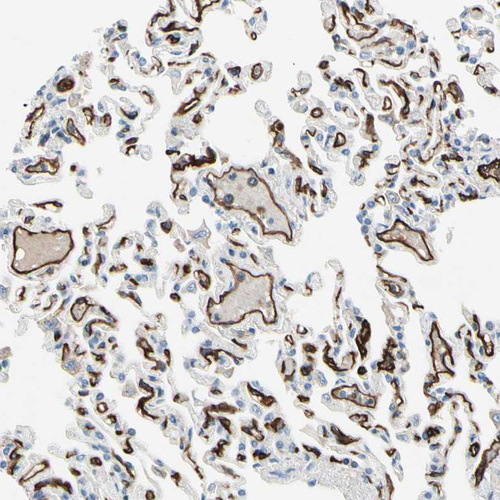

Immunohistochemistry analysis in human lung and skeletal muscle tissues using HPA009300 antibody. Corresponding CD93 RNA-seq data are presented for the same tissues.